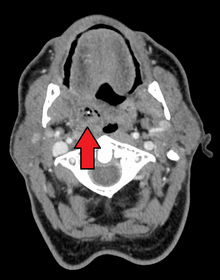

Peritonsillar abscess on the person's right as seen on CT imaging

PTA usually arises as a complication of an untreated or partially treated episode of acute tonsillitis. The infection, in these cases, spreads to the peritonsillar area (peritonsillitis). This region comprises loose connective tissue and is hence susceptible to formation of an abscess. PTA can also occur de novo. Both aerobic and anaerobic bacteria can be causative. Commonly involved aerobic pathogens include Streptococcus, Staphylococcus and Haemophilus. The most common anaerobic species include Fusobacterium necrophorum, Peptostreptococcus, Prevotella species, and Bacteroides.[2][3][4][5][6][7]